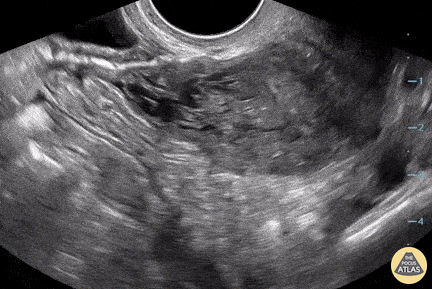

A 38-year-old female with PMH ulcerative colitis presented with several hour history of RLQ abdominal pain. Pain was described as sharp and constant; it woke her from her sleep. Vitals were WNL. Physical exam was notable for right adnexal tenderness and RLQ abdominal tenderness to palpation. Pelvic ultrasound revealed an enlarged right ovary with peripheralized follicles, heterogenous ovarian stroma, and peri-ovarian free fluid; findings concerning for ovarian torsion. It is important to remember that while ovarian torsion remains a clinical diagnosis, US grey scale findings are some of the most reliable radiographic adjunct predictors of the diagnosis as Doppler imaging often remains normal. Reference: Grunau GL, Harris A, Buckley J, Todd NJ. Diagnosis of Ovarian Torsion: Is It Time to Forget About Doppler? Journal of Obstetrics and Gynaecology Canada. 2018;40(7):871-875. Devin Peuser, @DevinPeuser Brooklyn, NY